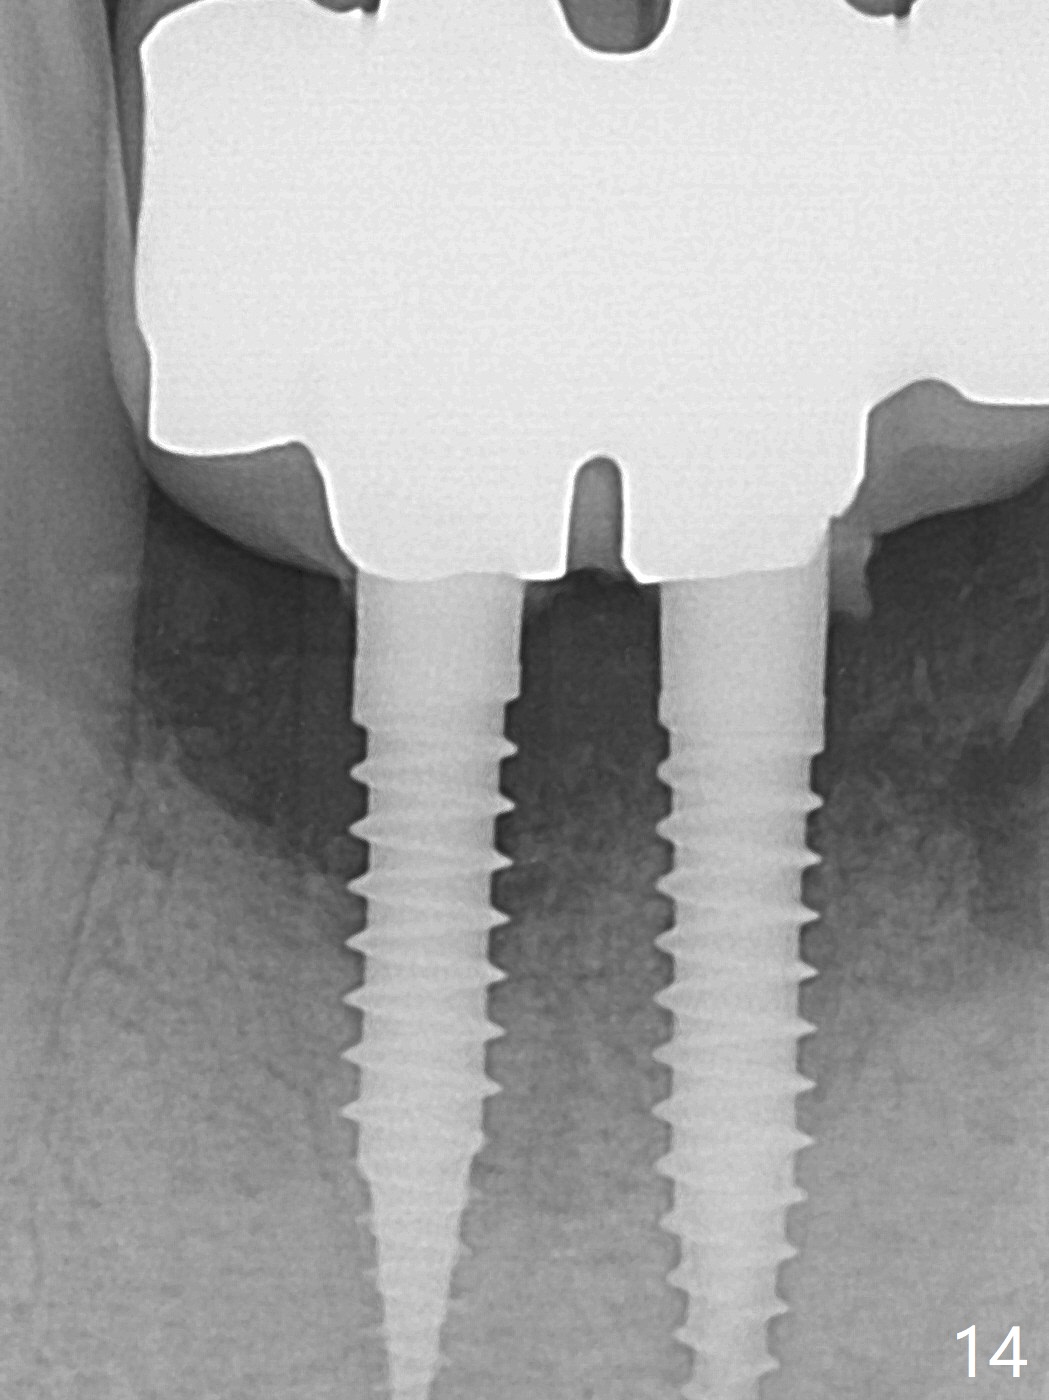

When the patient (smoker) returns for treatment, the apical abscess associated with #25 and 26 reduces with oral Amoxicillin. He agrees with 4 incisor extraction because of 2 apical fistulae (Fig.1 >). Osteotomy starts at the central incisor sockets due to mesial root exposure of the canines (Fig.2 arrowheads) and buccal alveolar bone fracture between #23 and 24 (Fig.7). Two of 3x14(4) mm 1-piece implants are placed with ~ 2 mm buccal gap (Fig.3). After Vanilla graft is placed in the bony defects (Fig.5 *) and Osteogen plug, sutures are placed (Fig.4). The implants are then placed deep to decrease thread exposure (Fig.6). Periodontal dressing is applied instead of provisional. Alveolar bone fracture between #23 and #24 accounts for why an implant is less suitably placed at #24 (Fig.7). Three months postop, composite is added to the pontic areas of the provisional (Fig.8 *). When the provisional is seated, the convex pontics press the used-to-be-flat gingiva (Fig.9 arrows). Thus the concave gingiva forms (Fig.10 *) with corresponding papillae (^). In fact the photos of Fig.8-10 is taken ~3 weeks later. Most of the grafted bone remains in place 3.5 months postop (Fig.11). A piece of floss with 2 knots in one end is placed between the middle units of the final bridge before cementation (Fig.12 (4 months 10 days postop)). In fact removal of residual cement is not so simple. It is tedious (Fig.13,14). An asymptomatic buccal fenetration with implant thread exposure is found 2 months post cementation and persists for another month in spite of advice to reduce smoking (1/2 ppd) and use of water pik (Fig.15). The area will be debrided, followed by bone graft and PRF in a month.